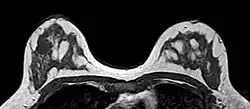

O sistema de relatórios e dados de imagem da mama (BI-RADS, do inglês Breast Imaging Reporting and Data System) é uma sistematização internacional para avaliação mamária, interpretação e laudos de exames de imagem da mama. No início, era utilizado apenas à mamografia, mas também é usado na ultrassonografia e ressonância magnética.[1]

- A categoria BI-RADS 1 quer dizer laudo de mamografia negativa, não há presença de massas ou calcificações suspeitas. As mamas são simétricas, sem massas, distorções de arquitetura ou calcificações suspeitas. Não há risco de câncer.

- A categoria BI-RADS 2 quer dizer laudo mamográfico contendo achados benignos, sem indicações de malignidade. Tem o risco do desenvolvimento de câncer idêntico ao BI-RADS 1, os médicos radiologistas decidem descrever os achados benignos incluindo fibroadenomas calcificados, calcificações múltiplas de origem secretora, cistos oleosos, lipomas, galactoceles e hamartomas de densidades mistas.

- A categoria BI-RADS 3 apresenta achados benignos menores que a categoria 2, e possuem pequena probabilidade de desenvolvimento maligno menor que 2%, recomenda-se fazer o controle semestral por 1 a 2 anos. Se nesse período continuar estável, será classificado como BI-RADS 2 (não há necessidade de realização de biópsia).